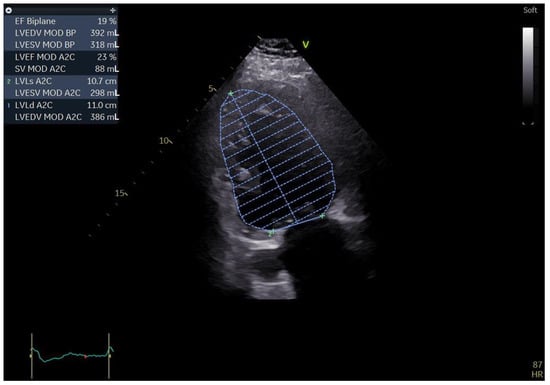

2. Case Report